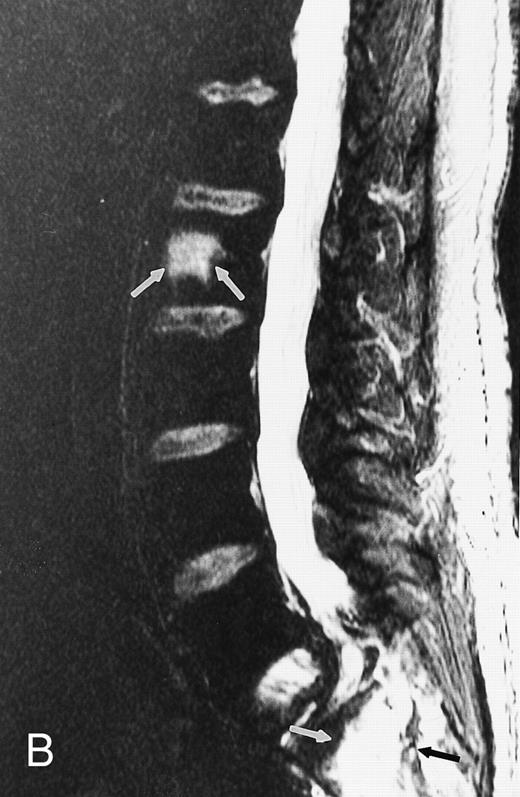

A 38-year-old man with solitary bone plasmacytoma and unsuspected lesions on MR images. Sagittal T1-weighted (600/20, TR/TE) MR image of the spine shows primary tumor in T12 (arrow) and additional focus of disease in L4 (short arrows). Conventional radiographs and CT scans failed to show the lesion in L2. Note characteristic postradiation bright signal in L1.